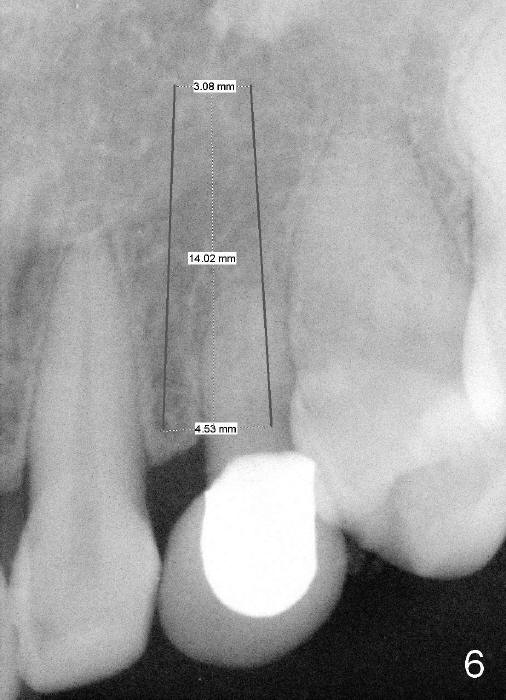

To improve cosmetics over the upper right canine immediate implant, a bone-level implant will be used (Fig.6) and an immediate provisional will be fabricated using a temporary abutment. Once osteointegrated, a gold-coated or porcelain abutment will be placed, depending upon the position of implant placement.